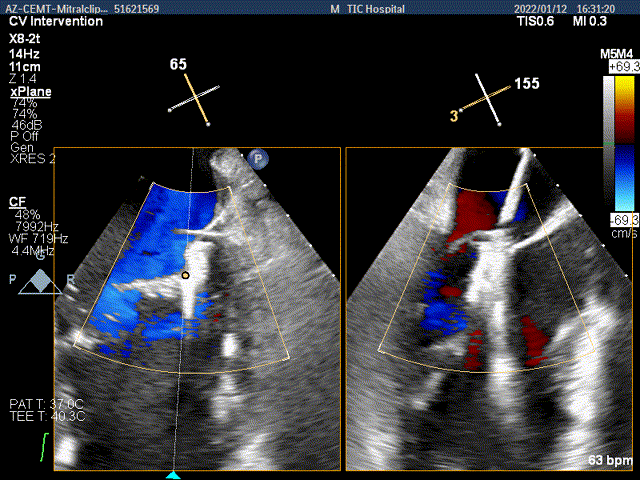

夹子关闭过程中,Color提示内侧1区残余返流

3D-color-VIEW验证残余返流来源

第一个夹子放置侯二尖瓣口平均跨瓣压差:2mmHg

肺静脉血流频谱逐渐恢复正向

x-plane验证前后叶抓捕后bond明显